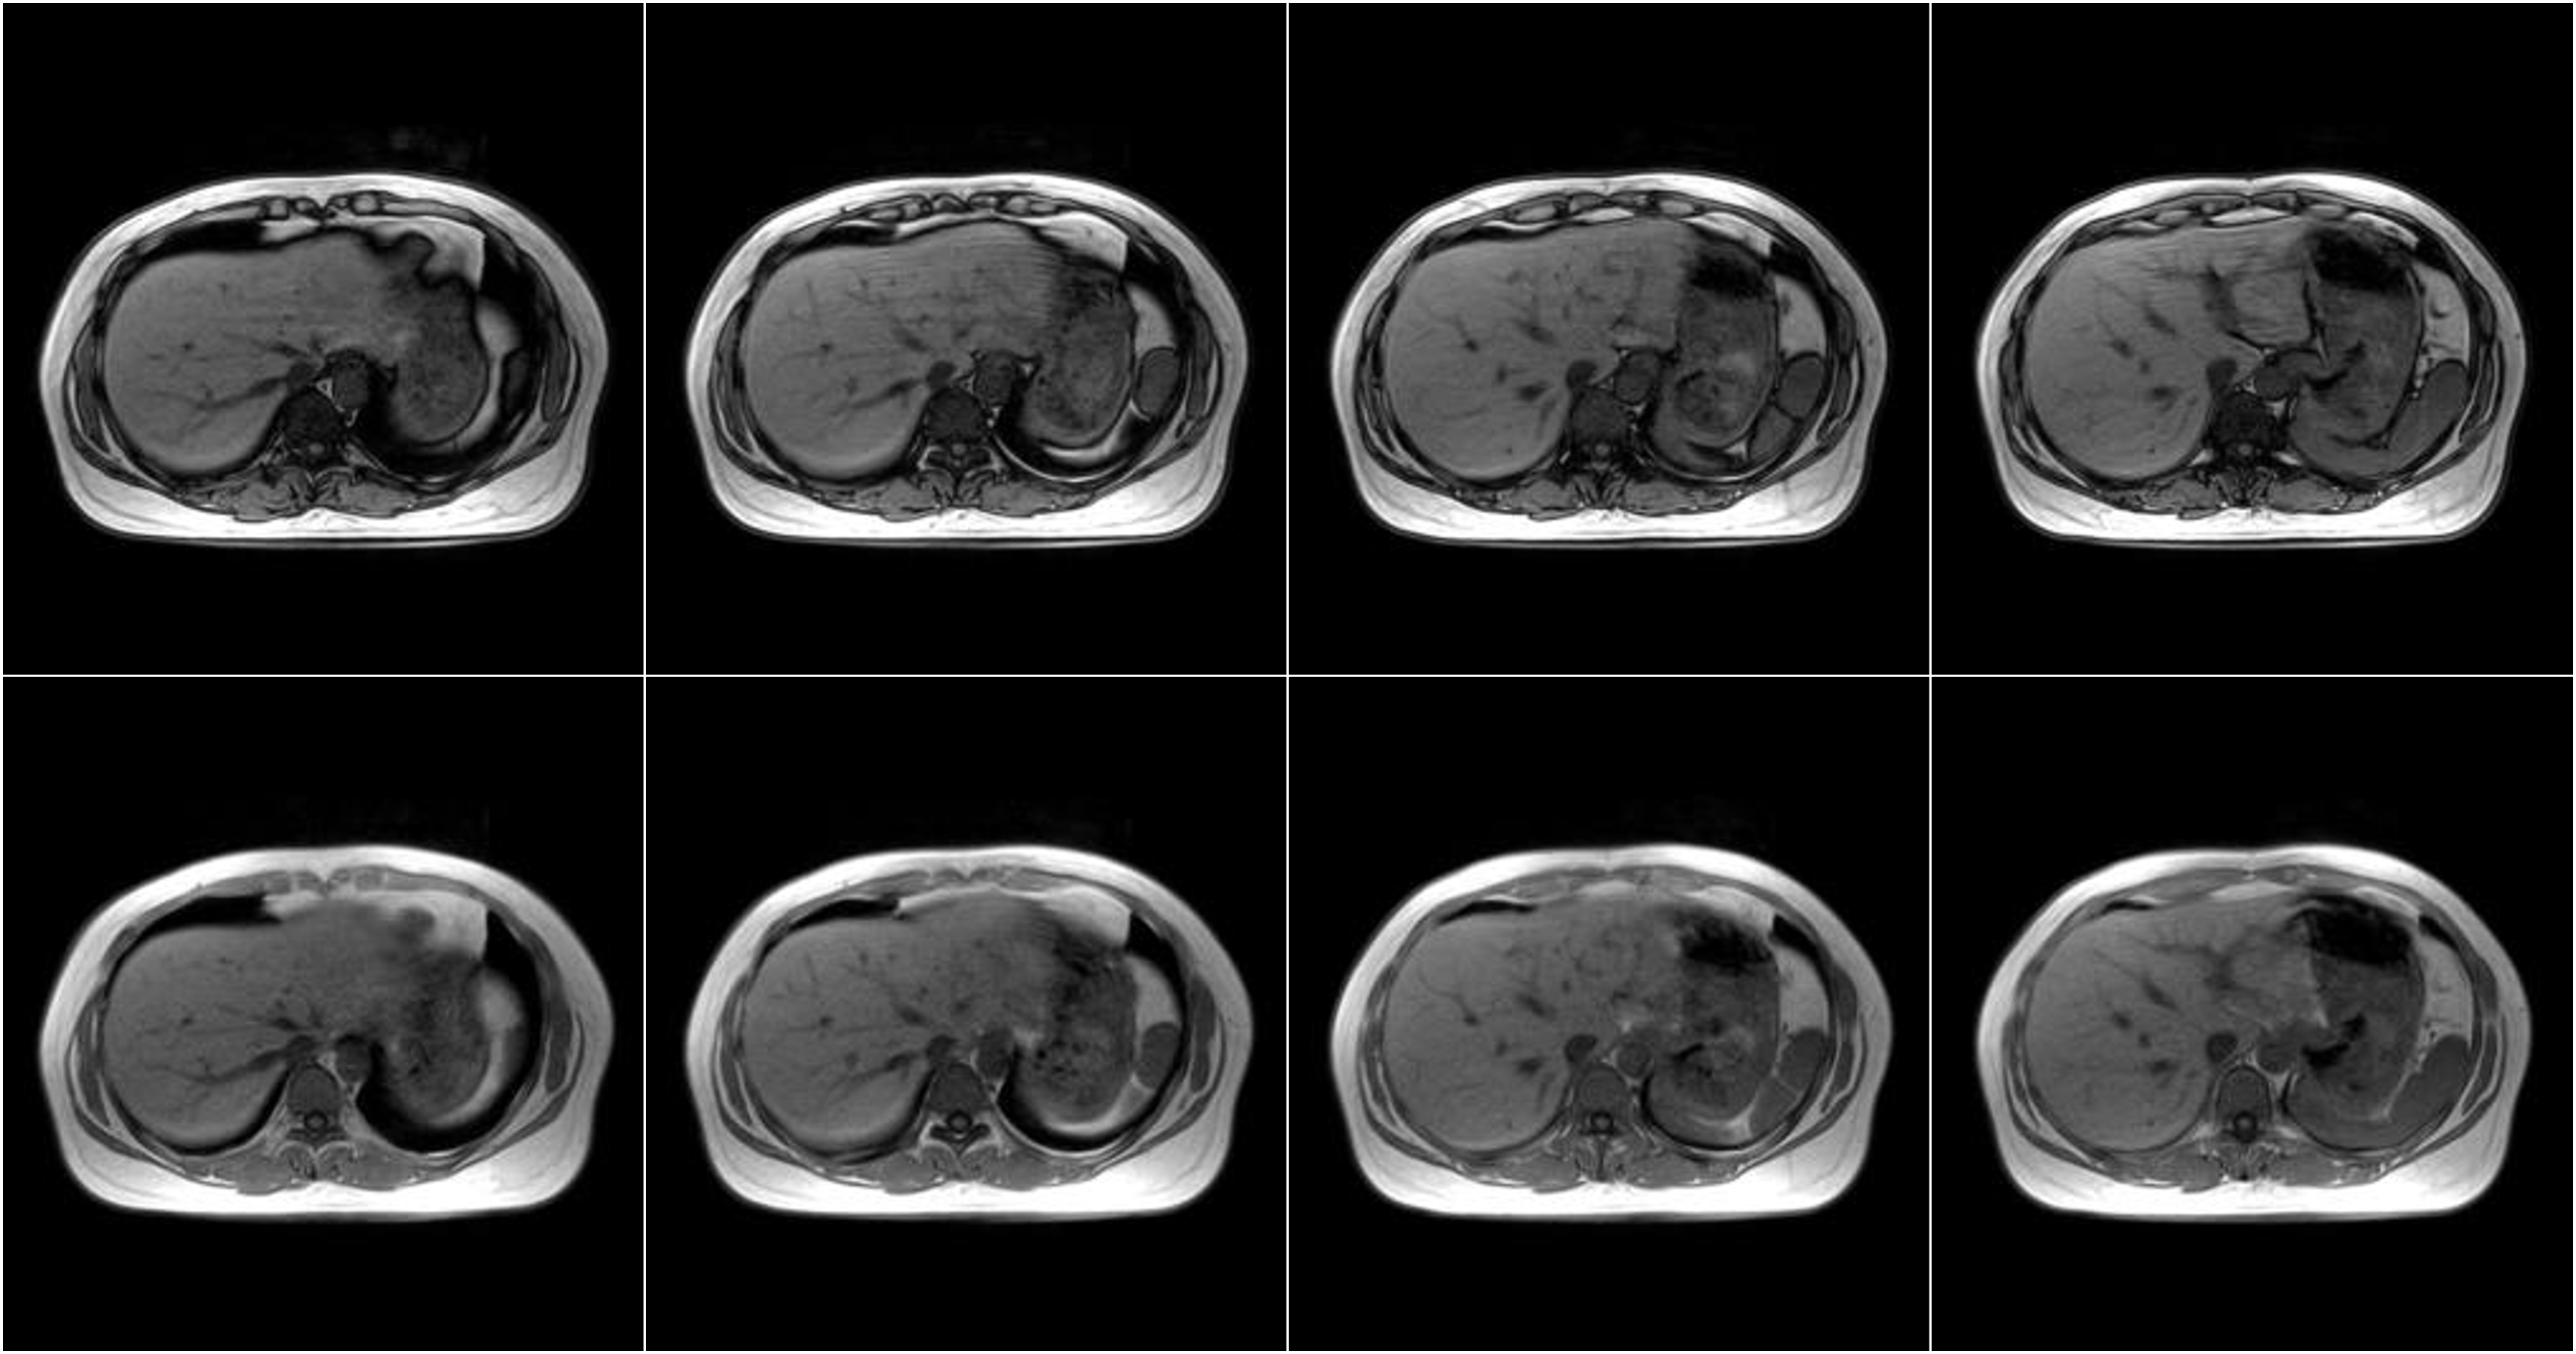

Hình ảnh lâm sàng